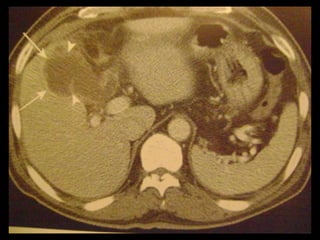

Colecistite aguda

US é a modalidade de imagem de escolha;

Em geral, a TC é realizada para avaliar pacientes

com suspeita de complicações do quadro de

colecistite aguda, como perfuração por exemplo.

Achados na TC: cálculos biliares, espessamento da

parede, alterações inflamatórias

perivesiculares, bile com alta

atenuação, borramento da interface VB-fígado e

aumento transitório da atenuação do fígado

perivesicular;